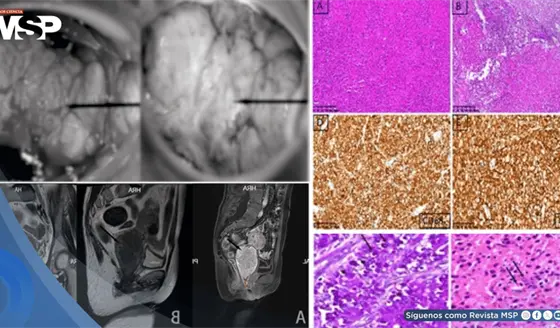

Malacoplaquia cervical simuló neoplasia maligna en mujer inmunocomprometida por miastenia gravis